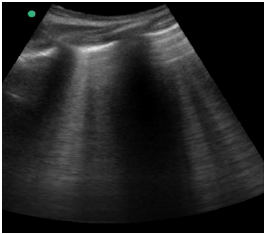

Um paciente de 40 anos de idade, vítima de queda de 9 metros (estava trabalhando quando o telhado cedeu), trazido à sala vermelha pelo SAMU, foi admitido com PA = 80 mmHg x 40 mmHg, FC = 120 bpm e tempo de enchimento capilar = 4 segundos. O emergencista procedeu ao e-fast, que evidenciou o achado apresentado na imagem.

Hemitórax esquerdo superior